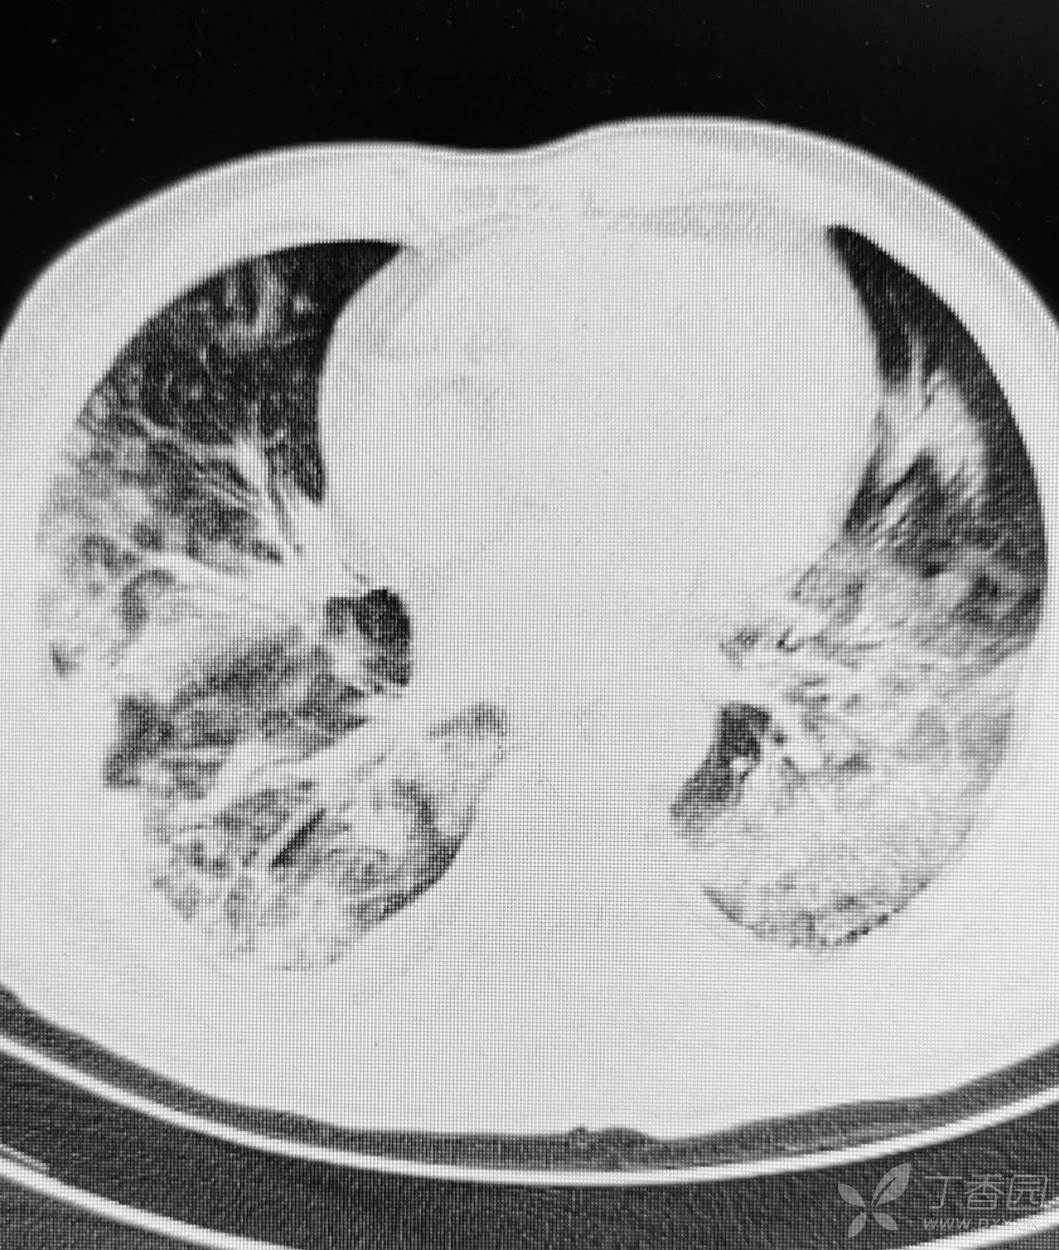

直肠癌术后两个月,接受放化疗一个月。白细胞危急值。

停化疗放疗,升白药物。白细胞增高了。

血小板仍低,血红蛋白开始降低。

胸部影像如图。

目前有血培养阳性,病原菌难以命中。痰培养阳性。